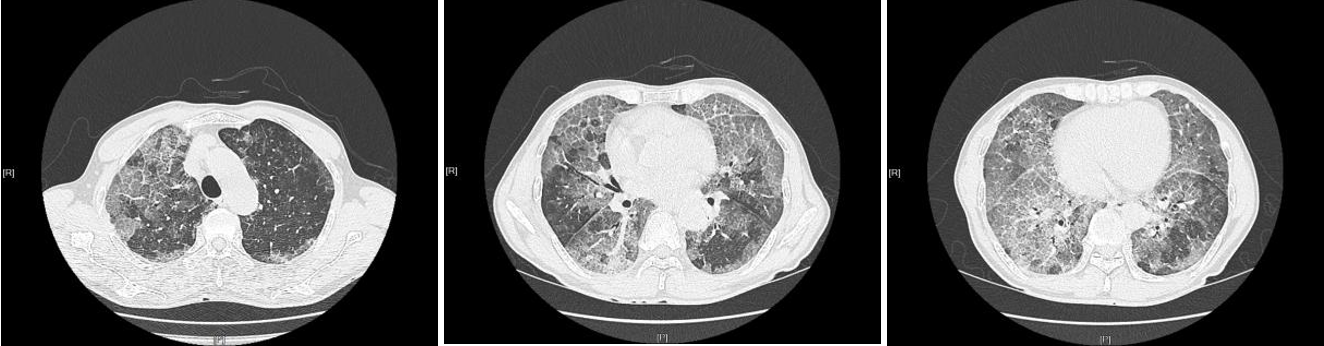

治疗前胸部CT:两肺多发磨玻璃阴影,典型的铺路石症

治疗后两肺渗出阴影明显吸收